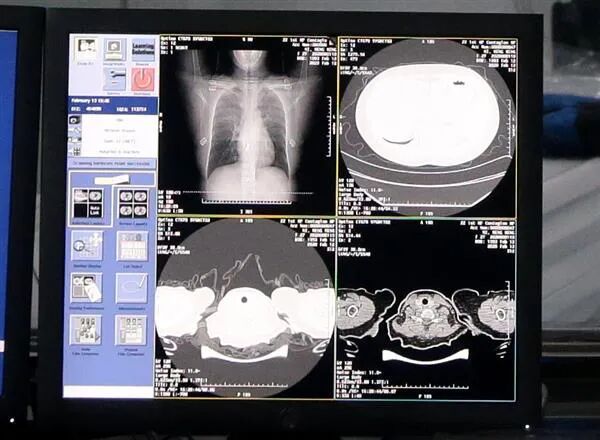

AI自动识别新冠肺炎病例CT胸片

以本次疫情之下

频频登上热搜的AI影像诊断为例。

对3万个临床疑似新冠肺炎病例CT影像进行了诊断,

单个病例影像分析可在20秒内完成,

准确率达96%。

判断病灶部位的占比比例、

量化病症的轻重程度,

从而提高诊断效率、减轻医护工作负担。